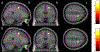

Results: The cancer group showed regional reductions over 12 months in frontal, temporal, and parietal gray matter on VBM, reduced FreeSurfer cortical thickness in prefrontal, parietal, and insular regions, and increased working memory-related fMRI activation in frontal, cingulate, and visual association cortex. Controls showed only reductions in fusiform gyrus on VBM and FreeSurfer temporal and parietal cortex thickness. Women with breast cancer showed higher estimated brain age and lower regional gray matter volume than controls at both time points. The cancer group showed a trend toward lower performance in attention, processing speed, and executive function at follow-up. There were no significant associations between brain imaging metrics and cognition or days on hormonal therapy.